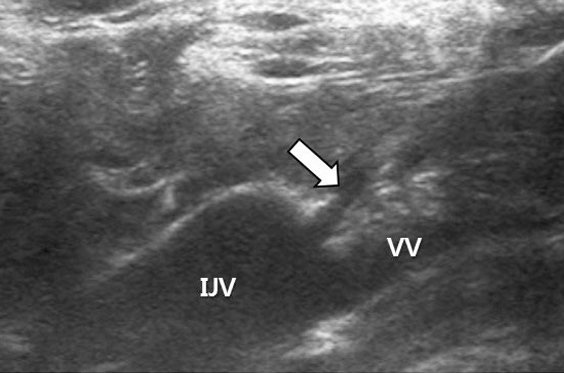

After sterile preparation of the neck and left chest wall, local anesthesia of the skin and subcutaneous tissue overlying the left internal jugular vein was performed by injecting lidocaine 2%. The left internal jugular vein was then punctured with a 19-guage needle under ultrasound guidance and a 0.035-inch guide wire with a J-tip was passed through the needle bore and directed into the right atrium under fluoroscopy. After creating a subcutaneous pocket in the left subclavian fossa which would harbor the infusion port, a tunneling device that attached to the infusion catheter was advanced through the subcutaneous layer from the pocket towards the venous access site. Following the tunneling maneuver, a stream of “milky”fluid was seen to spill out of the skin at the point of venous access (Fig. 1). This fluid was immediately recognized to be chyle and ultrasound was used to reveal the course of the guide wire traversing the cervical portion of the thoracic duct (Fig. 2). Before foregoing aggressive intervention, conservative management was attempted by manual compression after guide wire removal. In line with our expectations, stasis of chyle spillage was achieved with light compression for ten minutes. In order to complete the chemoport placement procedure, a new access was created in the left internal jugular vein, albeit a little more cephalad to the original puncture site. The chemoport was finally placed without complication.

Fig 2

Ultrasound demonstrating the thoracic duct (arrow) between the left internal jugular vein (IJV) and vertebral vein (VV). A guide wire (arrowheads) penetrating the thoracic duct is noted.

The true incidence of lymphatic injuries during central venous catheterization is unknown owing to the rarity of such complications. This is reflected by the scarcity of literature which is limited to isolated case reports [2-6]. Although fluid analysis was not performed in our case, the characteristic “milky”appearance of chyle was suggestive of thoracic duct injury and this was correlated on ultrasound. The thoracic duct is the largest lymphatic vessel in the body and drains almost of the body’s lymph. It is the common trunk for all the lymphatic vessels of the body, excepting those on the right side of the head, neck, and thorax, the right upper extremity, right lung, right side of the heart, and the convex surface of the liver. The thoracic duct usually terminates at the junction of the left internal jugular vein and left subclavian vein, a site that is commonly referred to as the jugulovenous angle [7,8]. In our case, ultrasound demonstrated the guide wire which had penetrated the cervical portion of the thoracic duct. The cervical portion of the thoracic duct is an anatomical landmark where the thoracic duct passes up and over between the left internal jugular and vertebral veins before it joins the jugulovenous angle. High-resolution ultrasound imaging with linear probes have been shown to be useful for visualizing the portion of the thoracic duct [9]. Although the use of ultrasound guidance has been shown to reduce the risk of complications that potentially occur during central venous catheterization, the presence of the thoracic duct may be overlooked without special attention. With regard to left-sided central venous catheterization, scrutiny during ultrasound guidance is mandatory, not only to avoid vascular complications, but also lymphatic injury. Interventional radiologists who commonly perform ultrasound-guided venous access in the neck region should be familiar with the anatomy of the thoracic duct and how it appears under ultrasound.